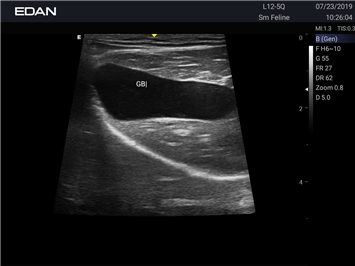

Ветеринарный ультразвук одним нажатием. Система Acclarix AX2 VET разработана с целью обеспечить бескомпромиссную производительность по доступной цене. Наличие уникальных двойных аккумуляторов в легком корпусе массой 4,5 кг из магниевого сплава позволяет системе Acclarix AX2 VET удовлетворять все потребности ветеринарных исследований, сохранив низкую стоимость.

EDAN Acclarix AX2 VET представляет собой специализированную ветеринарную ультразвуковую систему, сочетающую высокую производительность с доступной ценой. Благодаря продуманной конструкции и передовым технологиям, система обеспечивает качественную диагностику животных различных видов.

B-режим, Двухмерное сканирование:

Да